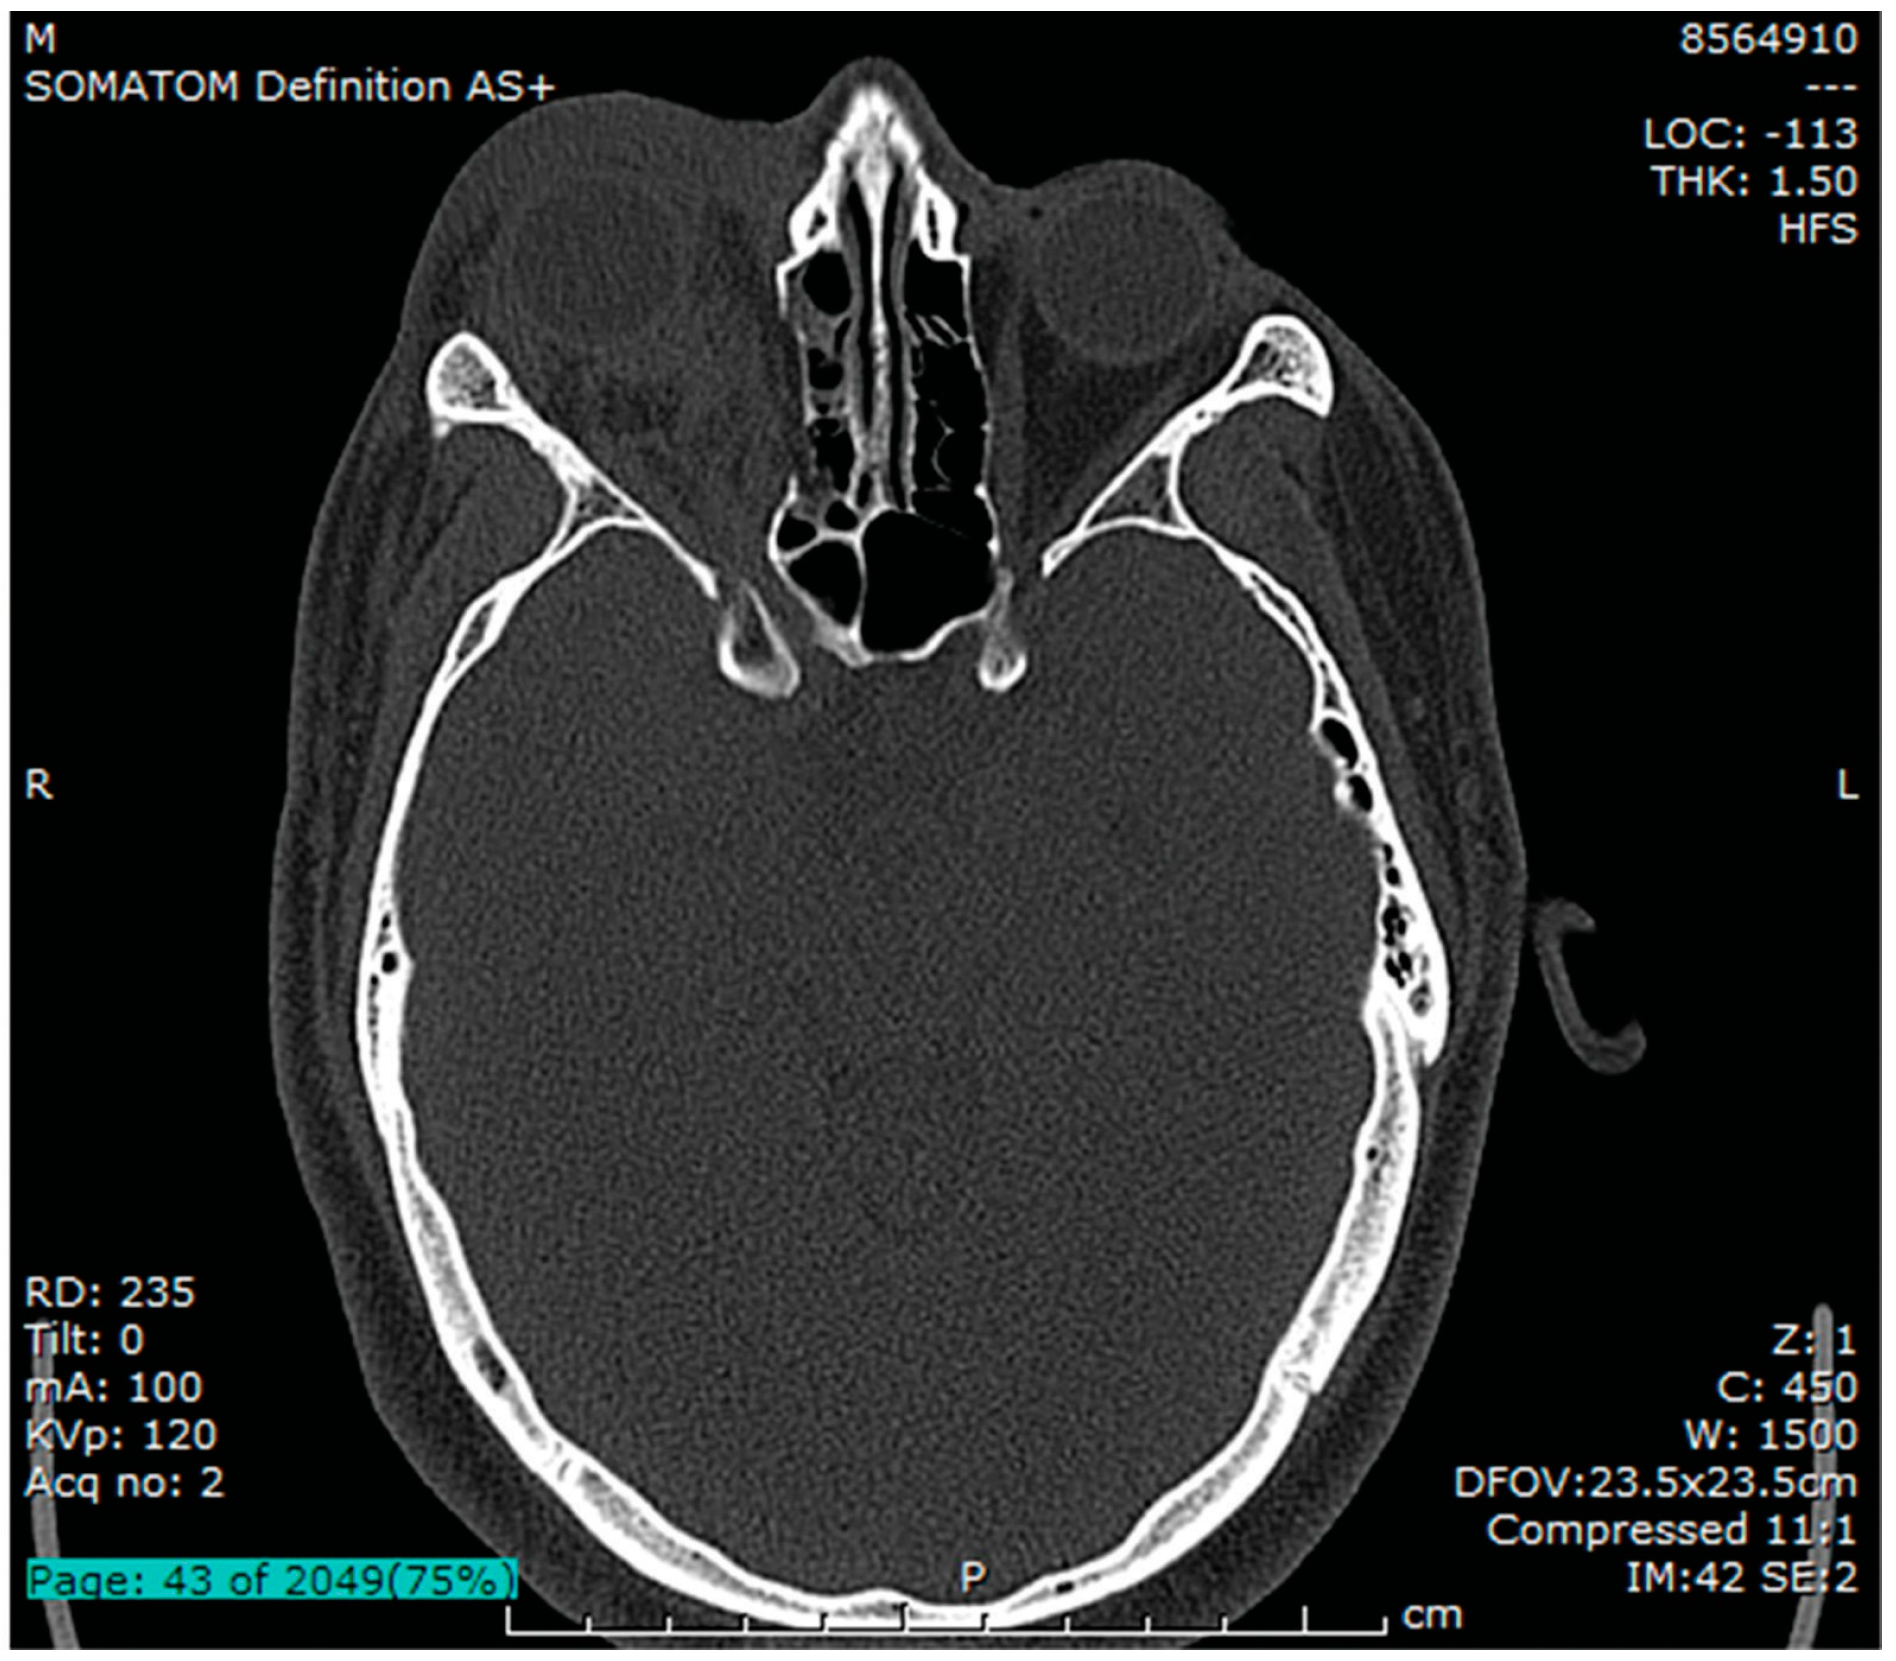

The postprocedure intraocular pressure was 23 to 29 mm Hg and there was a palpable reduction in orbital tension. Subsequent orbital imaging (Figure 1, Figure 2 and Figure 3) confirmed a displaced/punched-out fracture of the orbital floor (unhinged, type III) [1] with fracture of the medial wall, hematoma in the orbital compartment. The globe was entrapped between the orbital rim inferiorly, hematoma posterosuperiorly, and edematous preseptal tissue anteriorly. There was no orbital foreign body.

Figure 1. Axial CT bone window at the level of the superior orbital fissure showing collapse of the medial wall, right proptosis, retro-orbital hematoma, periocular soft-tissue edema.

This case represents an unusual situation wherein, despite a large type III orbital-floor blow-out fracture extending from the inferior orbital groove anteriorly to the apex posteriorly (Figure 2 and Figure 3), there remained significant globe compression. The globe was entrapped between the orbital hemorrhage posteriorly and superiorly, the anterior orbital rim inferiorly, and behind edematous soft tissue anteriorly. The critical signs were an overlapping mix of compartment compression and compartment fracture: an orbital mass effect (proptosis; increased orbital tension and intraocular pressure; mechanical ophthalmoplegia due to hemorrhage), functional compromise (diplopia due to ophthalmoplegia; possible reduction in VA; and an afferent pupil defect due to optic nerve compromise), and signs of orbital structural compromise of wall fracture (mechanical ophthalmoplegia due to incarceration of muscle; infraorbital nerve hypoesthesia; and oculocardiac-reflex–mediated bradycardia). A mixed presentation may be clinically suspected on evaluation of clinical signs, but the diagnosis will require imaging for confirmation. This should not delay its management.